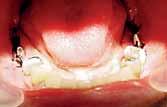

A 60 years old healthy female came into the clinic asking for a

fixed dental appliance to restore the bilateral edentulous posterior spaces of her own (Kennedy class 1).

There was a missing 6 and 7 on each side with compromised 4 and 5 on each.

The volume of available bone was insufficient to place a root form implant on the site of 7 (C-h available bone) a ridge mapping technique was used and a (C-w available bone) was also encountered.

The use of short implant in this case was not a treatment of choice; the crown - implant ratio is > 1.

A unilateral subperiosteal implant was suggested.